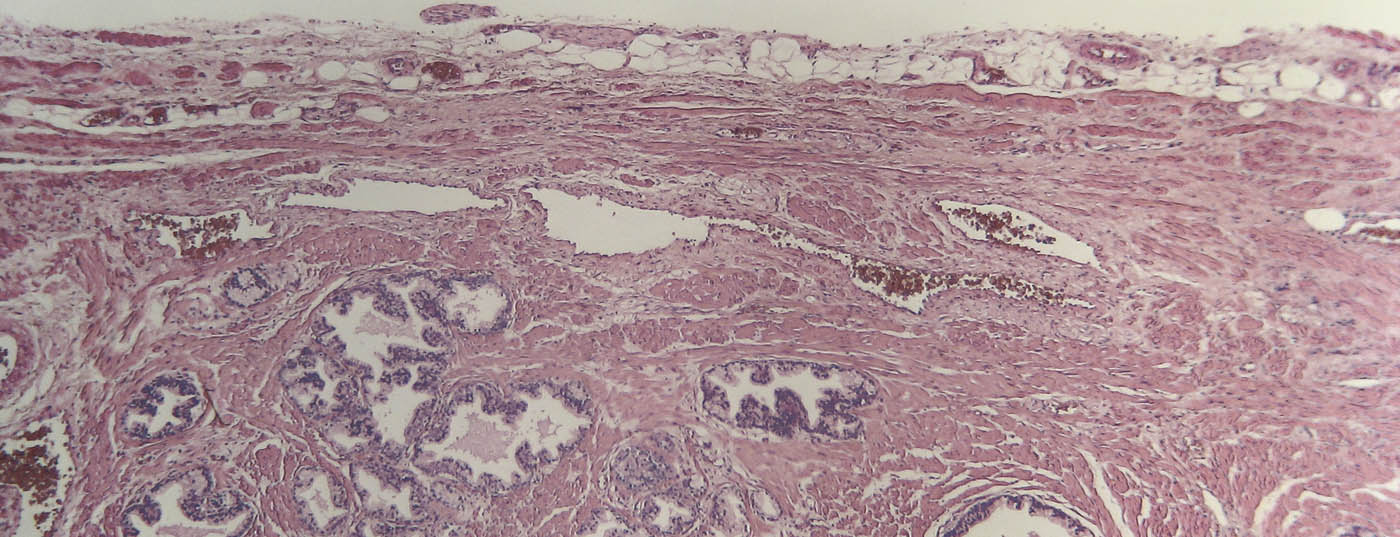

prostata_histo

• Therapie des lokalisierten Prostatakarzinoms

Brachytherapie mit permanenter, interstitieller Implantation von Jod-125

Die Leitlinien der europäischen und amerikanischen Urologen­gesellschaften zum lokalisierten Prostatakarzinom zeigen, dass die radikale Prostatektomie, die «Low Dose Rate» (LDR)-Brachytherapie und die externe Radiotherapie eine vergleichbare Effektivität bezüglich PSA-rezidivfreiem Überleben im Langzeitverlauf aufweisen. Der gut informierte Patient wird seine Therapie deshalb vorwiegend aufgrund der Neben­wir­­­kun­gen der Methode wählen. Die Datenlage bezüglich Harn­inkontinenz, erektiler Funktion, Blasenentleerungs­störung ­und Rektumtoxizität  ist jedoch spärlich und Vergleiche sind schwierig. In der Schweiz werden alle Brachytherapien seit 1. Januar 2005 prospektiv in einem nationalen Register ­erfasst. Die ­laufende Auswertung zeichnet ein durchwegs positives Bild für die LDR-Brachytherapie.